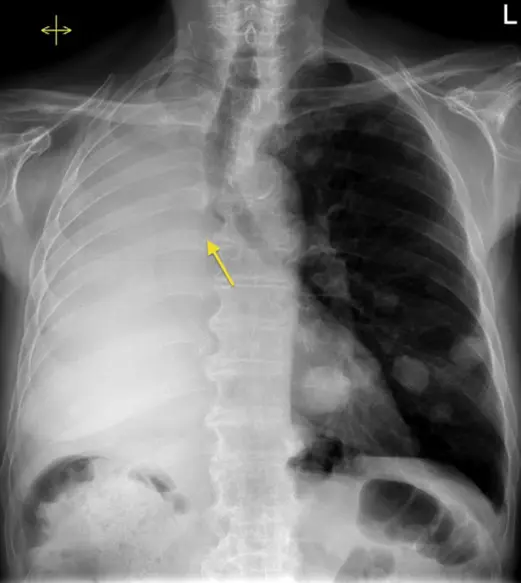

The 82-year-old Barry Manilow, a veteran vocalist, has unequivocally stated that he will have surgery after a thorough medical examination revealed the presence of lung cancer in him. The problem was unravelled through an MRI scan ordered after the singer had a long-lasting attack of bronchitis.

The doctors detected a malignant growth on his left lung and assured him that the disease had been caught very early. The early detection had a very positive effect on the prognosis because the doctors said that the cancer had not gone beyond the lung.

Doctors have opted to do Barry Manilow surgery on the focus points of cancerous left lung. The reason is that the diagnosis is placed under early-stage lung cancer treatment guidelines; thus, it is expected that surgery alone will be enough.